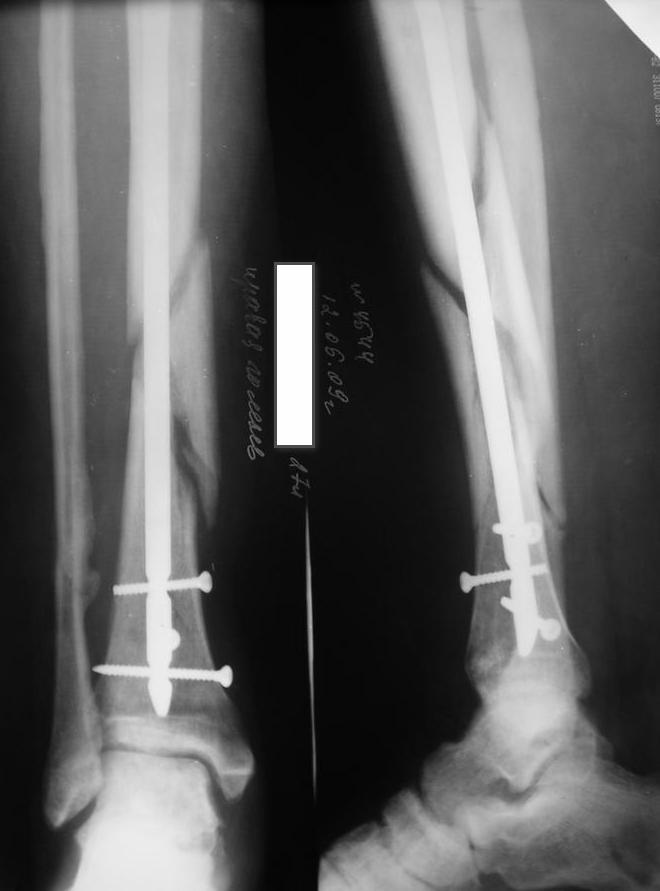

У нас был молодой пациент М.(26лет), травма 25 января 2009г, катался на лыжах и получил травму. Поступил к нам в отделение в экстренном порядке. При обследованиии выявлен закрытый винтоообразный оскольчатый перелом правой большеберцовой кости и косой перелом малоберцовой кости на границе средней и нижней трети. Выполнен интрамедуллярный блокируемый синтез большеберцовой кости, оси и длина конечности восстановлена. После операции пациент ходил с полной нагрузкой. Через 3 месяца на контрольных рентгенограммах сращения нет, динамизации не выполняли, так как оскольчатый перелом.(снимки в динамике прилагаются). Посоветуйте, что в данном случае делать наиболее целесообразно?

Остеосинтез, похоже, сделали с перерастяжением, так что динамизировать, наоборот, надо было еще и раньше обычного, недели через 4 после операции.

Да есть диастаз, но скорее от смещения осколка по ширине, а не по длине - по малоберцовой длина нормальна.

И малоберцовая перерастянута. По большеберцовой видно щель по переднему контуру, промежуточный фрагмент к этой области не имеет отношения.